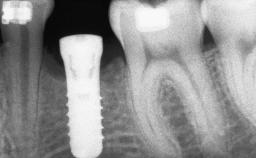

Bone Volume Deficient horizontally, requiring prior grafting